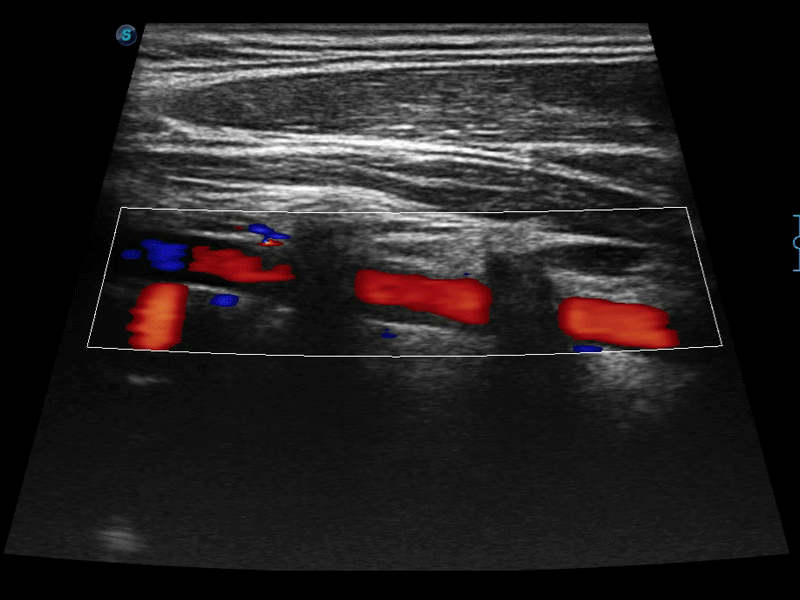

高分辨率血流成像技术提高了对低速血流信号的检测能力。在提高空间分辨率的同时,也克服了血流外溢现象,为用户提供更加真实的血流动力学信息。

凸阵、线阵和相控阵探头进行实时扫描时,开启扩展成像模式,可以扩展超声图像视野,以便更完整地查看大的病灶或组织器官的解剖结构。

通过色彩血流和实时宽景相结合,可观察到完整的静脉或动脉的血流,方便医生检查。实时扫查过程中,如有任何操作失误也可以很容易地进行回扫擦除,而不会中断扫查。